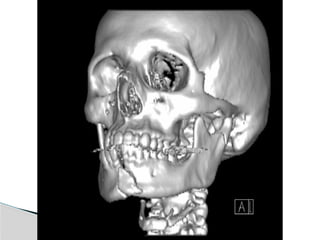

Classification (Lindhal, 1977)

 A) Fracture level

1) Condylar head( )

2) condylar neck

3) subcondylar (high or low)

 B) Relation of condyle to mandible

1) Non displaced

2) Diviated angulated

3) Displaced ( M or L/A or P overlap)

 C) Relation of condyle to glenoid fossa

1) Non dispalced

2) Displaced-still related to fossa

3) Dislocation-completely out of fossa (head

usually anteriomedial)

Classification (Lindhal, 1977) A) Fracture level 1) Condylar head( ) 2) condylar neck 3) subcondylar (high or low)

 B) Relationof condyle to mandible 1) Non displaced 2) Diviated angulated 3) Displaced ( M or L/A or P overlap)  C) Relation of condyle to glenoid fossa 1) Non dispalced 2) Displaced-still related to fossa 3) Dislocation-completely out of fossa (head usually anteriomedial)